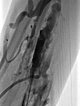

Entsprechend der relativ kleinen einzelnen Gefäßdurchmesser der venösen Malformation ist diese auch nur schwer direkt zu punktieren. Die Varikographie in Direktpunktionstechnik zeigt multiple, eher längliche, zum Teil netzartige dysplastische kleinlumige Venenkanäle.

Nach Sicherung der Nadellage innerhalb der venösen Malformation und Ausschluss eines Abstroms über eine größere Kommunikationsvenen, wird Polidocanolschaum (3% Äthoxysklerol 1 zu 4 in Luft aufgeschäumt) injiziert. Dieser Schaum ist nicht röntgendicht sondern verdrängt das vorher injizierte Kontrastmittel aus der Läsion.

Auch weiter proximal am Unterarm wird schrittweise die gesamte venöse Malformation in der Tiefe der Flexorenmuskulatur ausgeschäumt.